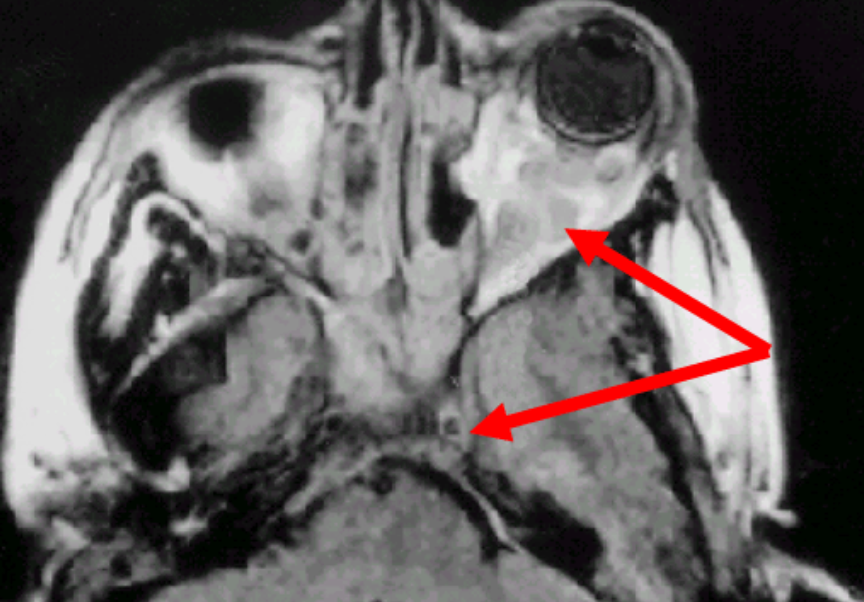

Define pre-septal cellulitis.

Infection in front of the orbital septum

Define Orbital Cellulitis.

infection of the soft issues of the eye socket behind the orbital septum

this is bad b/c the orbit infections lead directly to the brain cavity